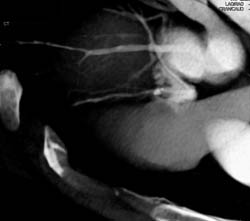

Diagnosis

Plaque in LAD